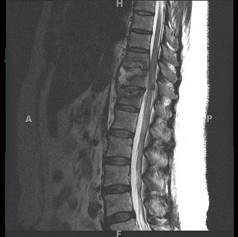

问题 女,67岁,突发右侧背痛半月余,请结合影像学检查,选择最可能的诊断 ( )

选项 A、脊椎结核 B、强直性脊柱炎 C、椎体压缩骨折 D、脊柱转移瘤 E、化脓性脊柱炎

答案 A